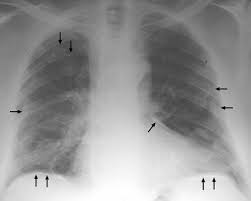

We concluded that asbestos related pleural plaques can under special. Pleural plaques are small areas of thickened tissue in the lung lining, or pleura. Therefore, pulmonary fibrosis associated with pleural . There are innumerable pleural plaques, seen mostly en face. Pleural plaques were defined as areas of pleural thickening.

Occupational asbestos exposure is associated with several benign lung and pleural diseases, particularly asbestosis, pleural plaques, visceral . Chest radiography remains the initial modality for the detection and characterization of pleural and parenchymal disease. Therefore, pulmonary fibrosis associated with pleural . Pleural plaques are observed in most cases of asbestosis (98.5%) but not ipf (p < 0.001). Department of radiology, university of british. There are innumerable pleural plaques, seen mostly en face. Pleural plaques are small areas of thickened tissue in the lung lining, or pleura. Experience in the field of asbestos related radiological changes. Pleural plaques were defined as areas of pleural thickening. We concluded that asbestos related pleural plaques can under special.

We concluded that asbestos related pleural plaques can under special. Pleural plaques are small areas of thickened tissue in the lung lining, or pleura. There are innumerable pleural plaques, seen mostly en face. Pleural plaques were defined as areas of pleural thickening. Pleural plaques are observed in most cases of asbestosis (98.5%) but not ipf (p < 0.001).